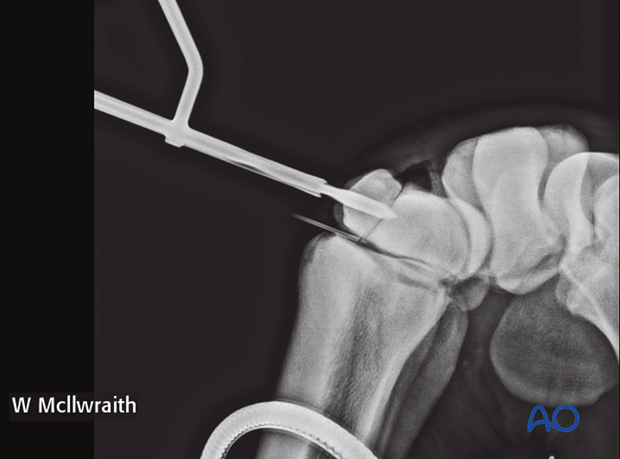

A flexed LM and ...

…skyline radiographic views are taken to provide the proximal-distal location of the lag screw.

Based on the radiographs two stab incisions are placed over the dorsal aspect of the radial and the intermediate facets respectively. Their positioning is based on radiographs of spinal needle placement.

Pearl: Use two fingers and thumb when doing final tightening, thereby avoiding excessive torque and potential breaking of screw head. Intraoperative radiographs are taken to confirm screw length and correct positioning.

Intraoperative radiographs are taken to confirm screw length and correct positioning.